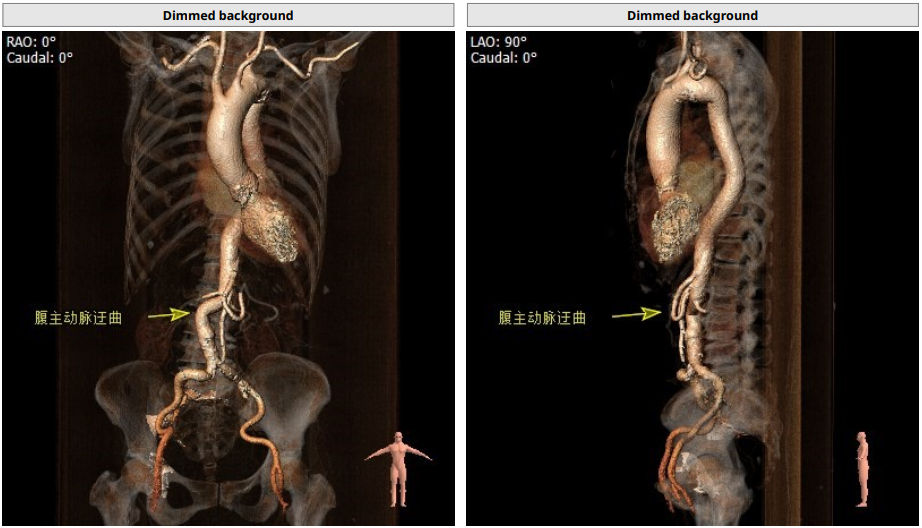

入路情况较为特殊,右股入路扭曲,左股尚可,腹主迂曲,上大鞘和过输送器时应轻柔,以防止血管并发症。决定左股作为主入路,左桡作为辅路。弓部呈锐角,过弓时应注意血管损伤,必要时借助抓捕器。